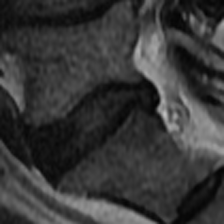

Lumbar Disc Degeneration (LDD) was found to be one of several reasons causing Low Back Pain [1]. Although there are several grading systems to quantify LDD, the Pfirrmann and Schneiderman scales are commonly used [2]. Pfirrmann et al. proposed a 555-scale grading system using T2-weighted MR imaging [3]. The grading system uses an algorithmic approach for LDD using signal intensity and disc homogeneity, demonstrated in Fig. 1. Over the past few years, several Deep Learning based methods were built to quantify LDD using MR imaging and the Pfirrmann grading system.

(a) PG 2

(b) PG 3

(c) PG 4

(d) PG 5

Fig. 1: Pfirrmann grades in L5-S1 as graded in the Northern Finland Birth Cohort dataset